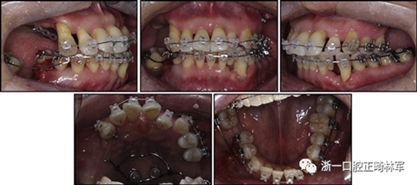

一名因多顆牙齒缺失和牙周損傷的49歲婦女被牙周科送往國民健康保險服務(wù)一山醫(yī)院的正畸科進行跨學(xué)科綜合治療。多顆后牙已在10天前被拔除。她的主訴是前牙列擁擠,她想改善美觀和功能。她的病史沒有提供有用信息,她沒有顳下頜關(guān)節(jié)紊亂的跡象。口外檢查顯示面部對稱,休息位時嘴唇不適,尖銳鼻唇溝和突出的嘴唇。她的下頜牙齒中線偏移到面部中線的左側(cè)(圖1)。

圖1. 治療前面部和口內(nèi)照片

口腔內(nèi)由于牙周炎,她的上頜右側(cè)第一和第二前磨牙,上頜右側(cè)第一和第二磨牙,上頜左側(cè)第一和第二磨牙以及下頜右側(cè)第一磨牙缺失。牙周探查顯示在磨牙區(qū)域和下頜骨左側(cè)側(cè)切牙區(qū)有深的牙周袋,還存在出血(表I)。上頜骨和下頜骨前牙擁擠,左側(cè)側(cè)切牙存在反合,下頜左側(cè)側(cè)切牙發(fā)過度萌出。覆蓋是5毫米,上頜切牙是唇傾的。在上頜弓中,尖牙和前磨牙是近中傾斜,右側(cè)尖牙過度萌出。而且,下頜右側(cè)第二磨牙向近中傾斜。尖牙處于I類關(guān)系,但無法評估磨牙關(guān)系(圖1和2)。